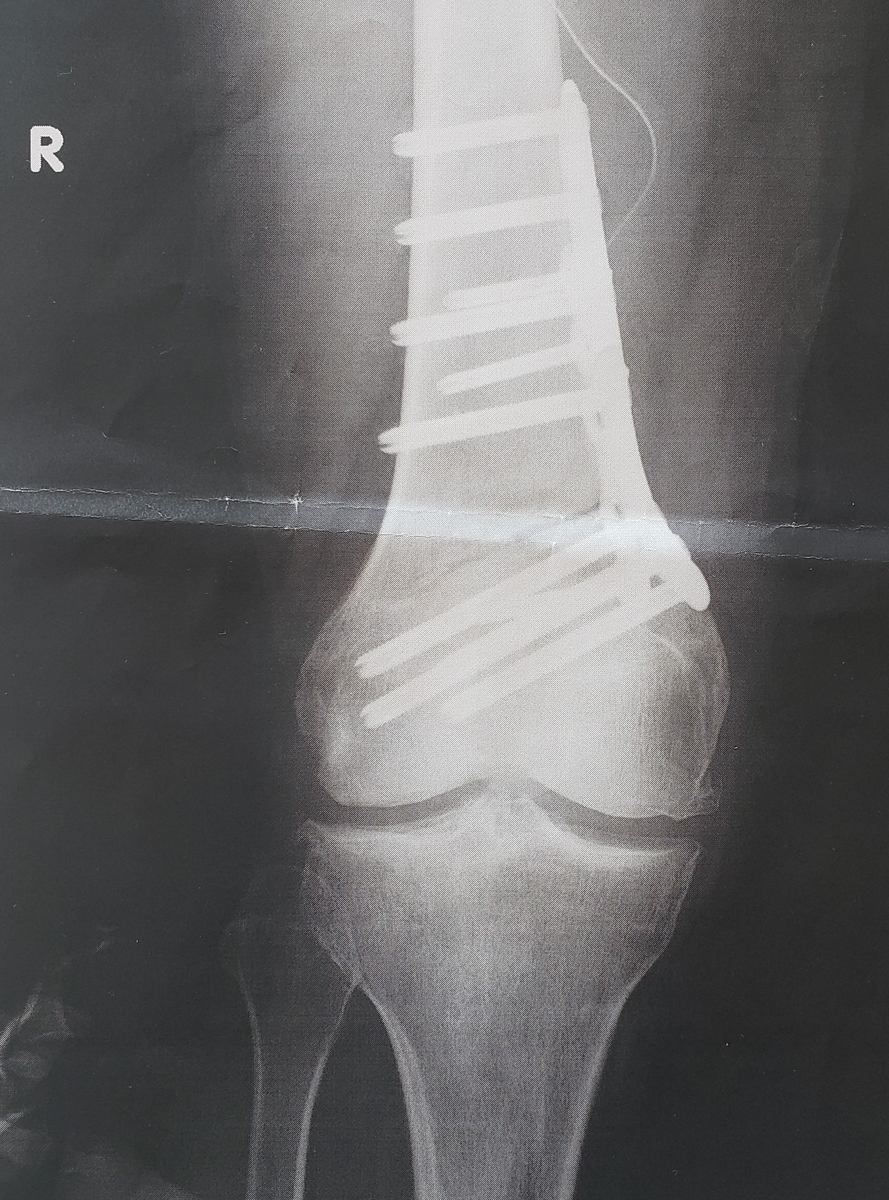

歩いてて突っ張った感じや、膝がぐらつく感じも、少しずつ解消されつつあるかなと。ま、手術から2か月経ちましたしね。